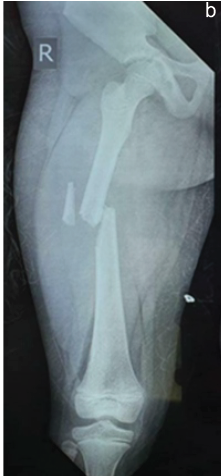

Outcome of Pediatric Femoral Shaft Fractures Treated with Titanium Elastic Nailing: A Prospective Study

Ismail Pandor , Abhishek Sharma , Anshuraj Jagdale , Alim Shaikh , Abhishek Doifode , Nilay Rank

………………………………p.399-404